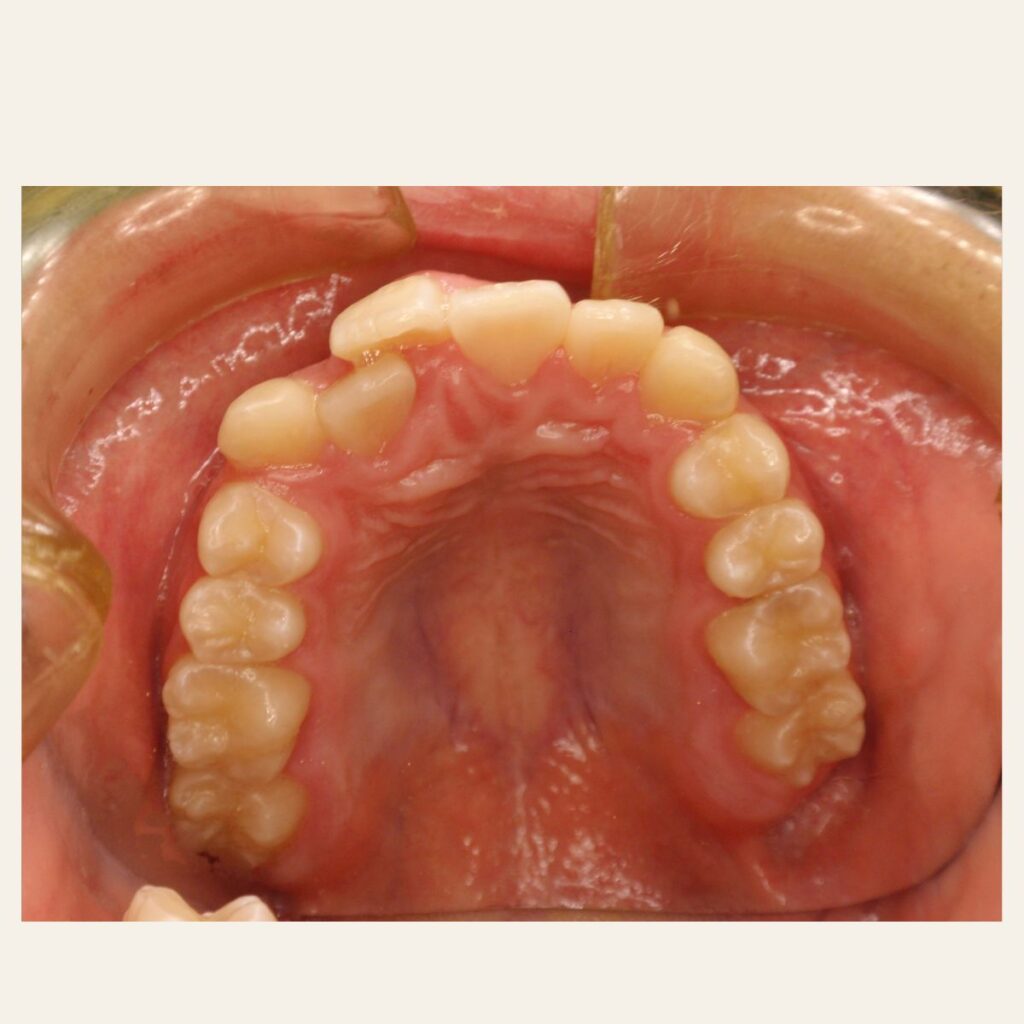

叢生の症例1(表側矯正)

治療前後(BEFORE/AFTER)

| 年齢 | 10代男性 |

| 主訴 | 前歯のガタガタ |

| 診断 | 叢生 |

| 治療方法 | 上下・表側ワイヤー矯正(今回抜歯はしていません) |

| 治療期間 | 11か月 |

| 費用 | 1,050,500円(税込) |

| リスク・副作用 | 痛み/歯根吸収/歯肉退縮/後戻り など |

本症例では歯が重なっている叢生と、前から見ると曲がっている状態でした。

歯列のスペースを確保しながら歯並びを整えるため、

表側矯正を用いて治療を行いました。

治療後は歯並びとかみ合わせが改善し、

見た目だけでなく歯磨きもしやすい状態になりました。

※虫歯の治療は矯正治療後に仕上げています。

※正中を合わせるには抜歯等が必要になる場合があります。